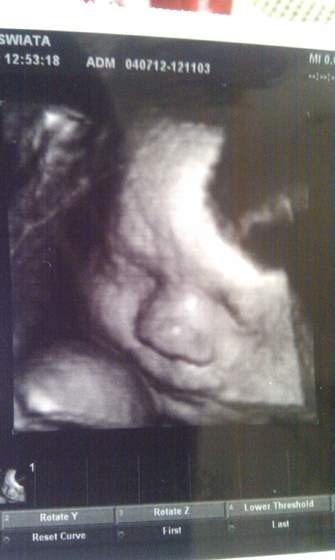

no a co do mojej wizyty to tak glówka jest na 32 tcnogi również i brzuś na 30 tc

no i wg wymiarow termin mam na ostatniego sierpnia